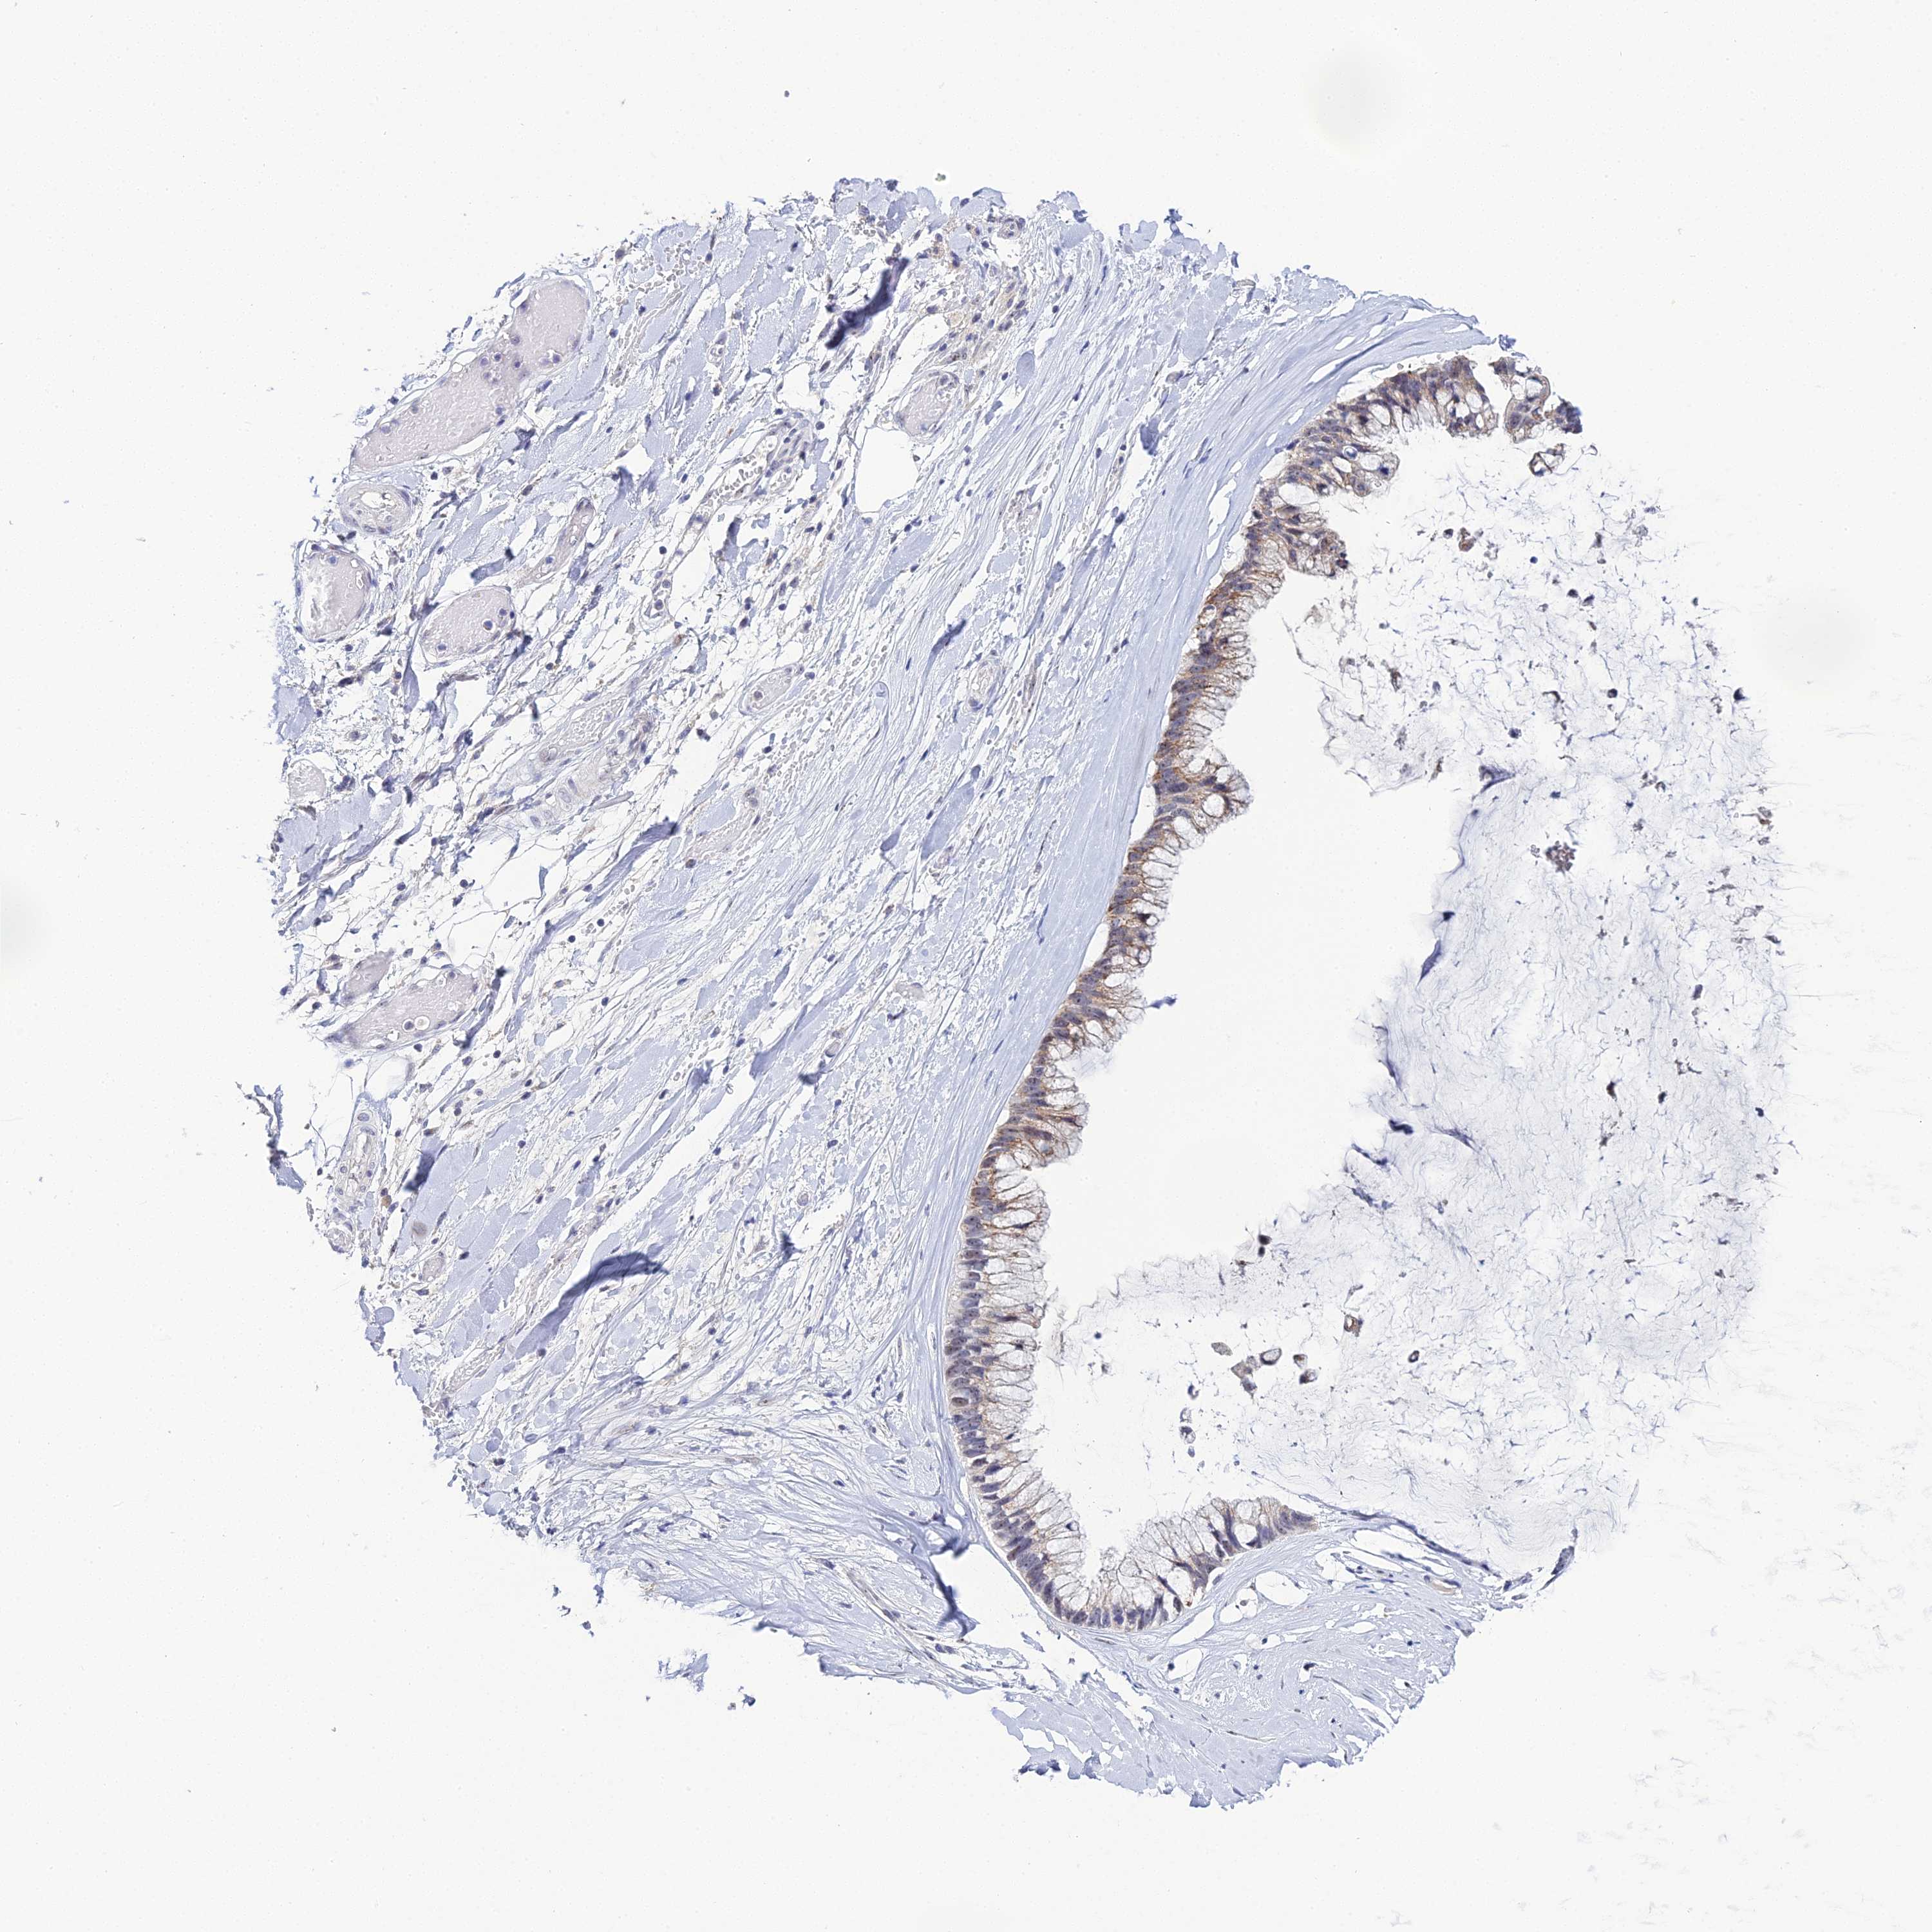

OVARIAN CANCER - Protein expressioni

A mouse-over function shows sample information and annotation data. Click on an image to view it in a full screen mode. Samples can be filtered based on level of antibody staining by selecting one or several of the following categories: high, medium, low and not detected. The assay and annotation is described here.

Note that samples used for immunohistochemistry by the Human Protein Atlas do not correspond to samples in the TCGA dataset.

Antibody stainingi

Antibody staining in the annotated cell types in the current human tissue is reported as not detected, low, medium, or high, based on conventional immunohistochemistry profiling in selected tissues. This score is based on the combination of the staining intensity and fraction of stained cells.

Each image is clickable and will lead to virtual microscopy that enables deeper exploration of all samples and also displays staining intensity scores, fraction scores and subcellular localization as well as patient and tissue information for each sample.

Antibody HPA045188

Staining

High

Medium

Low

Not detected

Intensity

Strong

Moderate

Weak

Negative

Quantity

>75%

75%-25%

<25%

None

Location

Nuclear

Cytoplasmic/membranous

Cytoplasmic/membranous,nuclear

Cystadenocarcinoma, serous, NOS

Carcinoma, endometroid

Cystadenocarcinoma, mucinous, NOS

Carcinoma, NOS